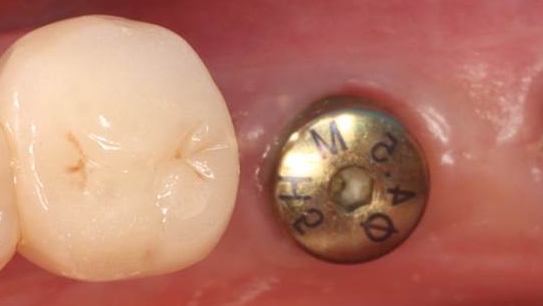

4. Wound status of Tooth #47 prior to the second-stage implant surgery (5 months post-implantation)

Completion of second-stage restoration: Healing abutment placement